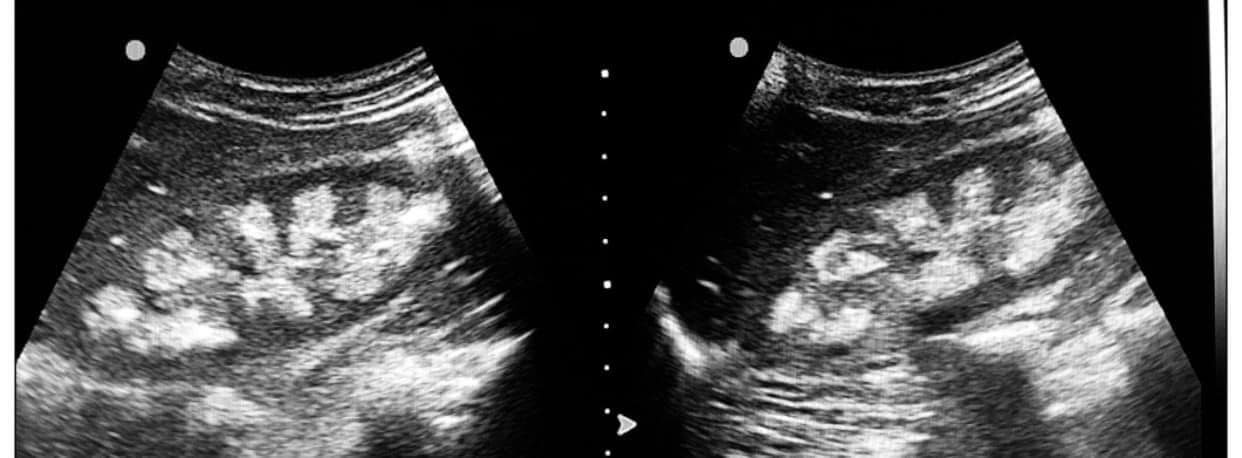

Đặc điểm hình ảnh: Các nốt vôi hóa nhỏ tụ thành đám trong từng tháp thận.

Lưu ý: Rất khó chẩn đoán bệnh lý thận nền dựa trên hình thái của vôi hóa, ngoại trừ các trường hợp: Hoại tử nhú thận do lạm dụng thuốc giảm đau vì toàn bộ nhú có thể bị vôi hóa, và Bệnh lí xốp tủy thận: là bệnh có thể thấy các vùng vôi hóa rõ và có phân bố không đồng đều.